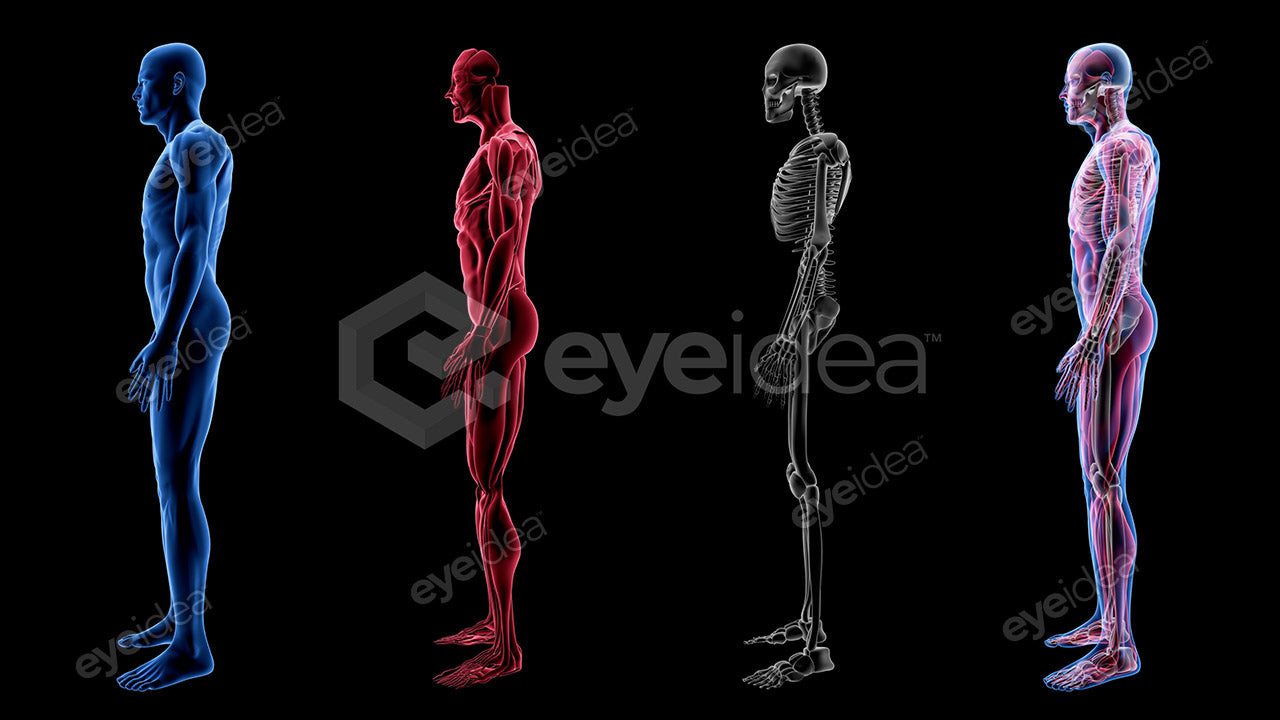

Versatility and Variety

Our Stock-Packs™ are curated to include a varied

range of angles, motion, styles and formats,

ensuring that creators can find the assets

they want fast and easy.